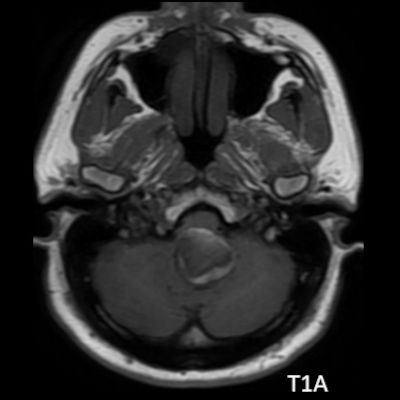

- A. Posterior fossada, T2A, T1A görüntü ve SWAN sekanslarda, 3.5 cm boyutta, düzgün sınırlı, T1A hiperintens, T2A hipointens heterojen iç yapıda kitlesel lezyon izleniyor (çember). Lezyonun serebellum ve kraniyoservikal bileşkeye bası etkisi mevcuttur (ok). Lezyon periferinde T1A, T2A ve SWAN görüntülerde hiperintens tubuler yapı bulunmaktadır (ok). Bu yapı intralezyonel “yılanvari eksantrik vasküler’’ yapıdır.

- Kısmen tromboze olmuş dev serebral anevrizma, kan ürünlerinin değişken yaşına bağlı olarak MRG’de heterojen bir sinyale sahiptir.

- T1 kısmen tromboze anevrizmada genellikle hiperintens odaklarla heterojen

- T2 kısmen tromboze anevrizmada genellikle hipointens odaklarla heterojen, serpantin anevrizma içi damar kanalında akım boşlukları, bitişik parankimde vazojenik ödem görülebilir.